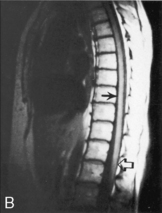

The child with EDH may demonstrate a lucid period that can last minutes to several days after the head injury. As the hematoma expands it compresses the temporal lobe, leading to an acute rise in ICP. The child may abruptly lose consciousness and demonstrate ipsilateral pupil dilation and contralateral hemiparesis. Left untreated, uncal herniation and death will result. Because an EDH is usually detected on an initial CT scan, the classic presentation is somewhat uncommon. Significant mortality and morbidity results if recognition or treatment is delayed.50,125

The best diagnostic test to confirm the presence of an EDH is a CT scan. Because the hematoma often is located directly under the skull fracture, plain skull radiographs may be adequate to localize the hematoma in a severely ill child. Most EDHs have the classic biconvex appearance on CT. A small percentage of EDHs have a crescent shape, and resemble an SDH. However, the edges of an EDH are usually sharp and the EDH has uniform density. Because the hematoma develops rapidly, there is almost always mass effect apparent on the CT scan. In rare cases the EDH may be isodense with the brain tissue and IV contrast must be used to identify the hemorrhage.50

Throughout the child's care, the nurse must be alert for signs of increased ICP (see Increased Intracranial Pressure). The sudden appearance of irritability, confusion, lethargy, and pupil dilation must be reported to a physician or other on-call provider immediately. Emergency acute management of sudden increases in ICP requires immediate intervention with support of the airway, oxygenation, and ventilation and administration of mannitol (0.5-1   gm/kg IV) or 3% saline (3-5   mL/kg IV bolus), or both. A CT scan is typically performed to detect any mass lesion requiring surgical intervention; the CT scan also will enable the evaluation of cerebral edema (see Fig. 11-12).20